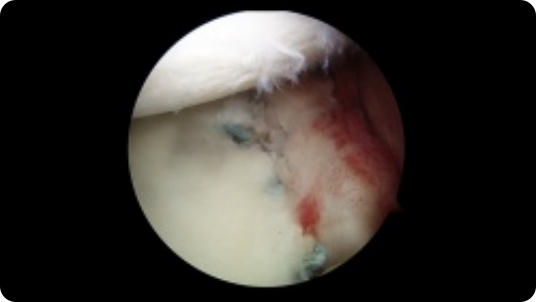

Arthroscopic image of a rotator cuff tear Arthroscopic image of a repaired rotator cuff

Rotator Cuff Tear